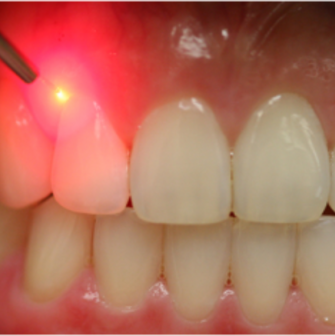

GENCIVE ET ESTHÉTIQUE

Lorsque vous souriez, vos dents vous semblent trop courtes. Il est possible que la solution ne soit pas d’allonger les dents mais plutôt de remonter votre gencive tel un « lifeting » afin qu’une partie plus importante de vos dents soit visible.

Un examen minutieux de votre sourire permettra d’évaluer si cette solution est pour vous. Plusieurs données seront prises, soit :

Nos dentiste pourront diagnostiquer la cause et trouver la solution pour vous :

- chirurgie mineure ou majeure des gencives (gingivectomie, greffe de tissu conjonctif, …);